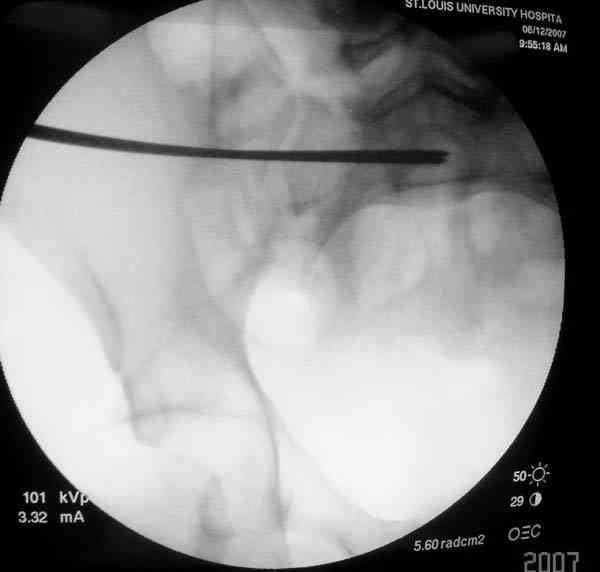

Применение длинных (7 мм каннюлированных, с резбой на всем протяжении от компании Mercury) шурупов, проведенных между двумя илиосакральными сочленениями нейтрализирует деформацию до наступления сращения.

На другом конце затягивание гайкой создает эффект болта-стяжки.

Сверло-направитель в 3.2 мм проводится вручную без применения дрели, и длина в 46 см обычно достаточна до захвата следующего илио-сактрального сочленения.

Sacroiliac screw placement

Inlet view

Проведение сверла под неврологическим мониторингом уменьшает риск повреждения нервов во время операции.

SI potential monitoring